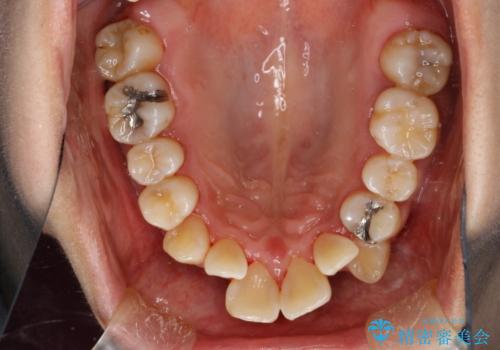

- これから矯正治療を始めるため、今の状態でも歯をきれいにしておきたいとのことでした。PMTC60分コースを行いました。

プラーク(細菌の塊)や歯石がたまると歯の表面はザラつきいてきます。そのザラつきは歯周病や虫歯菌の棲家となります。そのまま放置すると、歯肉が腫れてきたり、歯肉から出血したり、口臭が強くでたりします。とくに歯肉の境目は、歯磨きで汚れを除去することが難しく、プラーク(細菌の塊)や歯石が溜まりやすい場所です。

歯並が、がたついている場合はなおさら汚れが溜まりやすいです。矯正治療前や矯正中、定期的にPMTCをすることで、矯正治療中の歯肉トラブルを防ぐことにつながります。